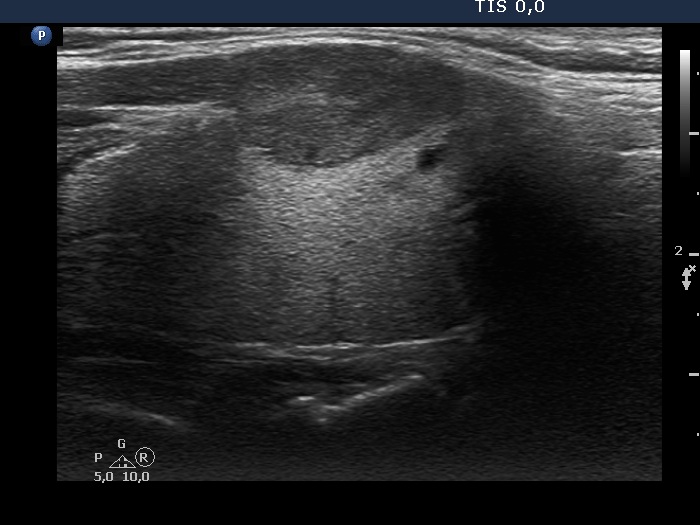

Study on 100 consecutive patients with thyroid nodule - case 009 (ultrasonographic picture 7)

Right side of the isthmus, longitudinal scan. The nodule presents the two possible signs of extrathyroidal extension, the contours are abutting and bulging. The third sign, the discontinuation of the capsule cannot be judged because the capsule lacks in most parts of the thyroid.